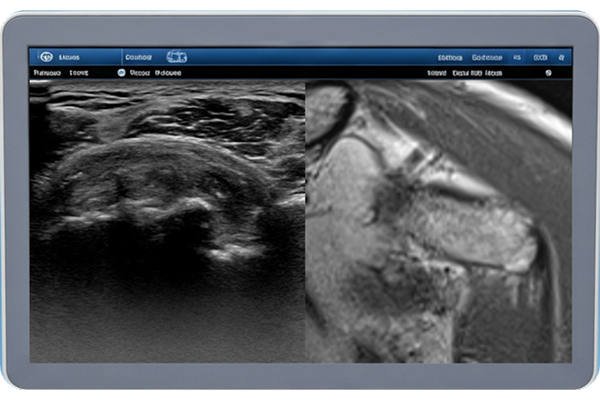

핵심기술초음파 이미지/영상을 MRI급 이미지/영상으로 합성하는 AI 기술 및 서비스

- 초음파 영상의 미세한 음영과 패턴을 분석하여 MRI에 버금가는 고해상도 및 이미지를 합성하는 기술

- 초음파 영상 속에서 해부학적 의미를 파악하고 그에 기반하여 임상적으로 유의미한 구조적 정보 생성하는 기술